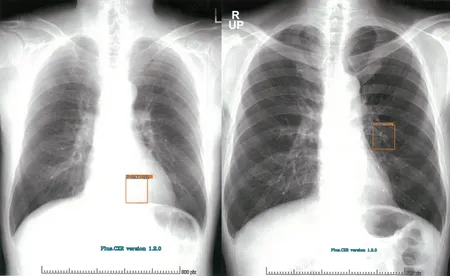

プラスマン合同会社

Plus.Lung.Nodule (CT-AI)は胸部CT画像に関心領域を表示し、肺結節やリンパ節等の視認性向上を図るプログラム医療機器です。

本製品は胸部単純X線写真の読影の際に医師に診断補助となる情報を提供するAIです。